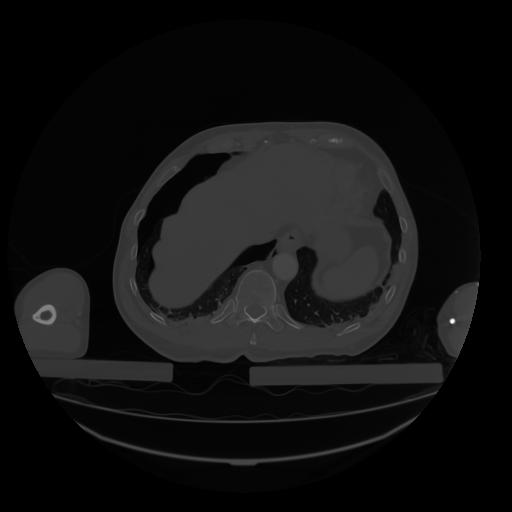

28 CUERPO,CE,Vol,2.0,CUERPO,,